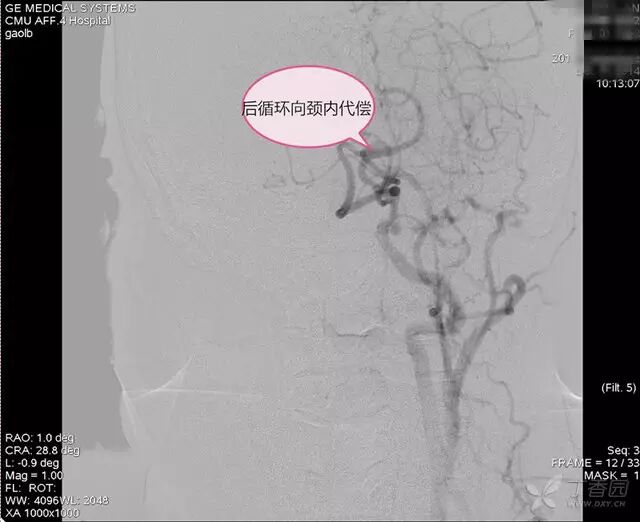

DSA:右锁骨下动脉起始部狭窄,狭窄率 96%,右椎动脉血流前向,右胚胎性大脑后动脉,左颈总动脉闭塞,左后交通动脉开放,后循环经左后交通动脉向左颈内动脉代偿,左甲颈干经左颈外动脉向左颈内动脉供血区代偿(图 1~4)。

图 4. 后循环向颈内代偿